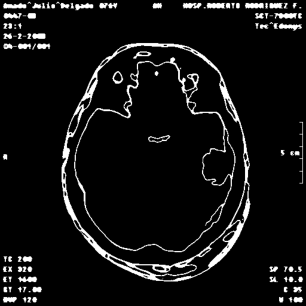

An example of an applications of our proposed strategy to a medical image is shown in Figure 7. In this case, we used different values of and in the . This is a preliminary result. A deeper paper about these results will be published.